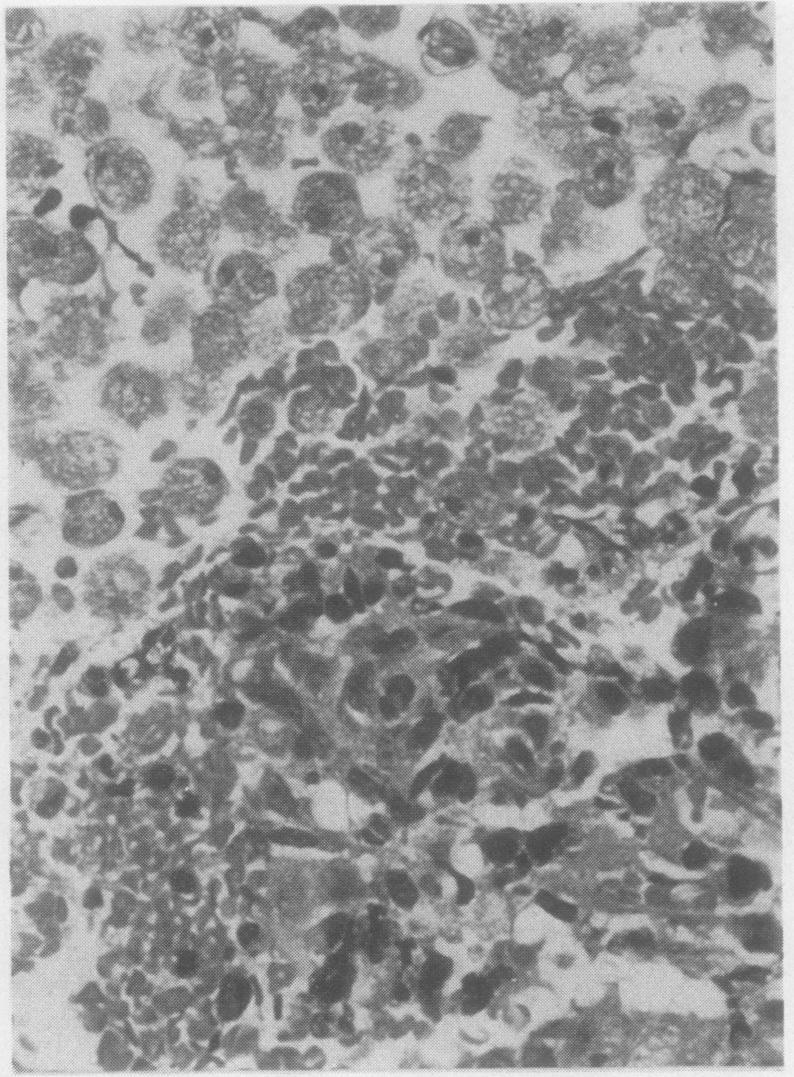

Opportunistic protozoan infections in human immunodeficiency virus disease: review highlighting diagnostic and therapeutic aspects.

摘要